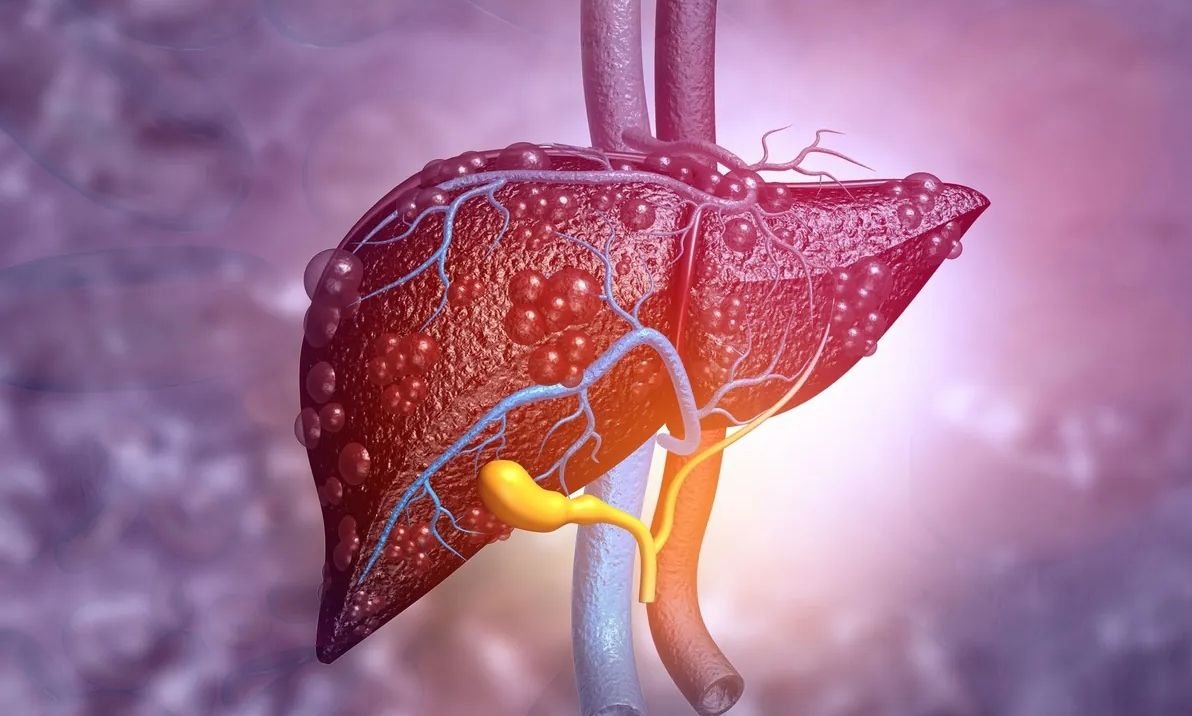

Ο λόγος είναι ότι εάν το ήπαρ αποθηκεύει υπερβολική ποσότητα ενέργειας με τη μορφή λίπους, αυτό μπορεί να οδηγήσει στη λεγόμενη μη αλκοολική λιπώδη νόσο του ήπατος.

Υπερβολικές ποσότητες λίπους αποθηκεύονται στον ιστό, με αποτέλεσμα το όργανο να μην λειτουργεί πλέον σωστά. Περίπου το 30% του παγκόσμιου πληθυσμού πάσχει από μη αλκοολική λιπώδη ηπατική νόσο.

Ένα μη αλκοολικό λιπώδες ήπαρ αναπτύσσεται συνήθως σταδιακά ως συνέπεια ενός ανθυγιεινού τρόπου ζωής επί πολλά χρόνια. Εκτός από μια διατροφή πλούσια σε λίπος και ζάχαρη, παίζουν επίσης ρόλο η έλλειψη άσκησης, ορισμένα φάρμακα και η υπερβολική κατανάλωση αλκοόλ.

Εάν η κύρια αιτία του λίπους στο συκώτι είναι η υπερβολική κατανάλωση αλκοόλ, οι γιατροί αναφέρονται σε αυτό ως αλκοολικό λιπώδες ήπαρ. Κάποιες μεταβολικές διαταραχές και άλλες ασθένειες μπορούν επίσης να προκαλέσουν τη συσσώρευση λίπους στο συκώτι.

Εάν ένα λιπώδες ήπαρ μείνει χωρίς θεραπεία, οι συνέπειες είναι καταστροφικές. Αρχικά, ο ηπατικός ιστός μπορεί να φλεγμαίνει και να νεκρώνεται μερικώς. Στα μεταγενέστερα στάδια, υπάρχει κίνδυνος κίρρωσης του ήπατος ή/και καρκίνου του ήπατος.

Ο λόγος είναι ότι εάν το ήπαρ αποθηκεύει υπερβολική ποσότητα ενέργειας με τη μορφή λίπους, αυτό μπορεί να οδηγήσει στη λεγόμενη μη αλκοολική λιπώδη νόσο του ήπατος.

Υπερβολικές ποσότητες λίπους αποθηκεύονται στον ιστό, με αποτέλεσμα το όργανο να μην λειτουργεί πλέον σωστά. Περίπου το 30% του παγκόσμιου πληθυσμού πάσχει από μη αλκοολική λιπώδη ηπατική νόσο.

Ένα μη αλκοολικό λιπώδες ήπαρ αναπτύσσεται συνήθως σταδιακά ως συνέπεια ενός ανθυγιεινού τρόπου ζωής επί πολλά χρόνια. Εκτός από μια διατροφή πλούσια σε λίπος και ζάχαρη, παίζουν επίσης ρόλο η έλλειψη άσκησης, ορισμένα φάρμακα και η υπερβολική κατανάλωση αλκοόλ.

Εάν η κύρια αιτία του λίπους στο συκώτι είναι η υπερβολική κατανάλωση αλκοόλ, οι γιατροί αναφέρονται σε αυτό ως αλκοολικό λιπώδες ήπαρ. Κάποιες μεταβολικές διαταραχές και άλλες ασθένειες μπορούν επίσης να προκαλέσουν τη συσσώρευση λίπους στο συκώτι.

Εάν ένα λιπώδες ήπαρ μείνει χωρίς θεραπεία, οι συνέπειες είναι καταστροφικές. Αρχικά, ο ηπατικός ιστός μπορεί να φλεγμαίνει και να νεκρώνεται μερικώς. Στα μεταγενέστερα στάδια, υπάρχει κίνδυνος κίρρωσης του ήπατος ή/και καρκίνου του ήπατος.